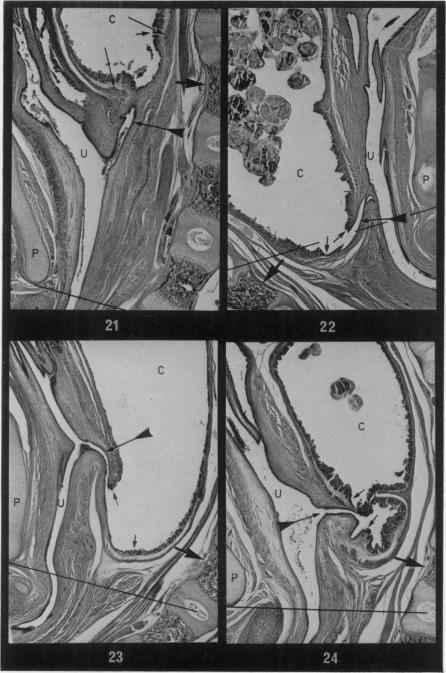

Among 906 thalidomide exposed young from 6 different rabbit strains, 141 major malformations involving the alimentary tract were found. All but 4 of the defects can confidently be regarded as a drug effect. The lesions occurred in the derivatives of the foregut, hindgut and umbilicus. Foregut anomalies (68 specimens) comprised hiatus hernia, megaoesophagus, prepyloric notching of the greater curvature of the stomach and deficient septum formation between oesophagus and trachea. In many rabbits all 4 lesions were present together. Hindgut malformations (61 specimens) were made up of rectal atresia and a small number of diverticula and/or saccular dilatations of the terminal colon, some in company with atresia. The 32 examples of atresia which were examined in detail had a coexistent fistula extending to the urethra or the anus. Omphalocoele (6 specimens in one strain) was the umbilical defect. It is suggested that some of the lesions result from impeded septum formation in the laryngotracheal grouve and the cloaca.

在来自6种不同兔种的906只接触沙利度胺的幼兔中,发现了141例涉及消化道的严重畸形。除4例缺陷外,其余均可确定为药物作用所致。这些病变发生在前肠、后肠和脐的衍生物中。前肠异常(68例标本)包括食管裂孔疝、巨食管、胃大弯处幽门前切迹以及食管与气管之间的隔膜形成缺陷。在许多兔子中,这4种病变同时存在。后肠畸形(61例标本)由直肠闭锁以及少数末端结肠憩室和/或囊状扩张组成,有些伴有闭锁。对详细检查的32例闭锁病例进行分析,发现均伴有延伸至尿道或肛门的瘘管。脐膨出(一个兔种中有6例标本)是脐部缺陷。有人认为,某些病变是由于喉气管沟和泄殖腔中隔膜形成受阻所致。